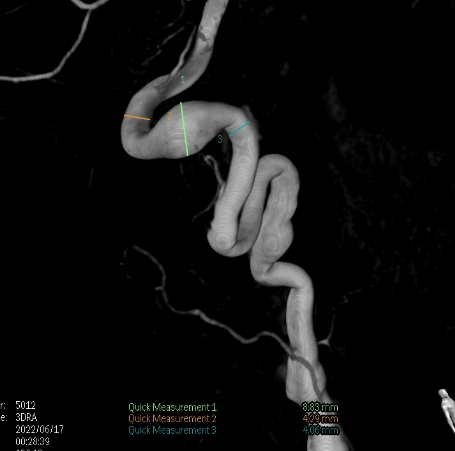

右侧大脑中动脉瘤,瘤颈处发出颞支,颈宽3.79mm,瘤高3.51mm,远近端载瘤动脉直径分别为2.43mm、2.52mm。

• 畅医达(Choydar)血流导向装置3.0mm*15mm